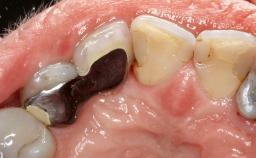

Paolo Casentini demonstrates that peri-implantitis can be successfully treated even at an advanced stage. He discusses a case in which the existing implants and prostheses were both retained while regenerating the defect and creating a band of keratinized tissue. A 69-year-old female patient was referred by her general dentist for evaluation of a recurrent infection at previously placed and restored implants in the posterior left mandible. The patient’s chief complaint was recurrent swelling and pain in the molar region of the left posterior mandible with discomfort during brushing in the same area. The patient reported receiving two implants (36 and 37) nine years earlier.